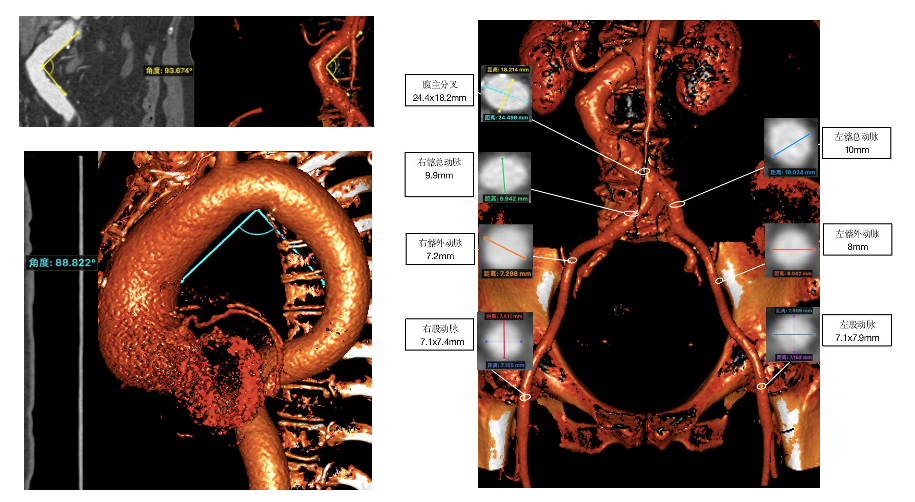

主动脉CT

主动脉根部形态,横位心明显

降主动脉及腹主动脉双重严重扭曲

入路:左右股动脉均在7mm以上,推荐右股动脉为主,

备注:极度横位心,建议结合抓捕器使用;降主动脉与腹主动脉严重扭曲,